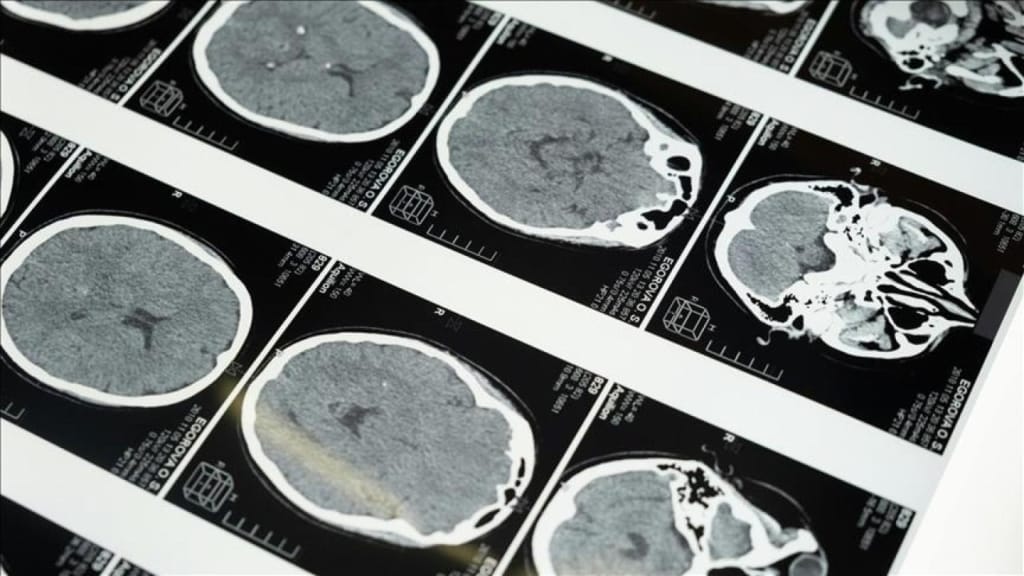

İstanbul’da gerçekleştirilen 1. Dünya Girişimsel Nöroloji ve Nöroşirürji Kongresi’nde (WINNC 2025) yer alan Eskişehir Osmangazi Üniversitesi Tıp Fakültesi Nöroloji Ana Bilim Dalı Öğretim Üyesi ve İnme Merkezi Sorumlusu Prof. Dr. Atilla Özcan Özdemir, inmenin beyin damarlarının tıkanması (iskemik) ve beyin kanaması şeklinde iki türü olduğunu belirtti.

Türkiye’de inme tedavisinde önemli ilerlemelerin yaşandığını ifade eden Özdemir, “Özellikle pıhtıyla tıkanan beyin damarının açılmasıyla ilgili stratejiler geliştirildi. İnme tedavisinde erken dönemde yapılan damar açma tedavileri konusunda ülke olarak iyi durumdayız. İnme merkezlerinde uygulanan bu işlemle hastaların hayatlarını normale döndürebiliyoruz. Bu müdahalelerin ilk 24 saat içinde yapılması çok kritik. Ancak bu tür müdahaleler sadece inme merkezlerinde gerçekleştirilebiliyor.” şeklinde konuştu.